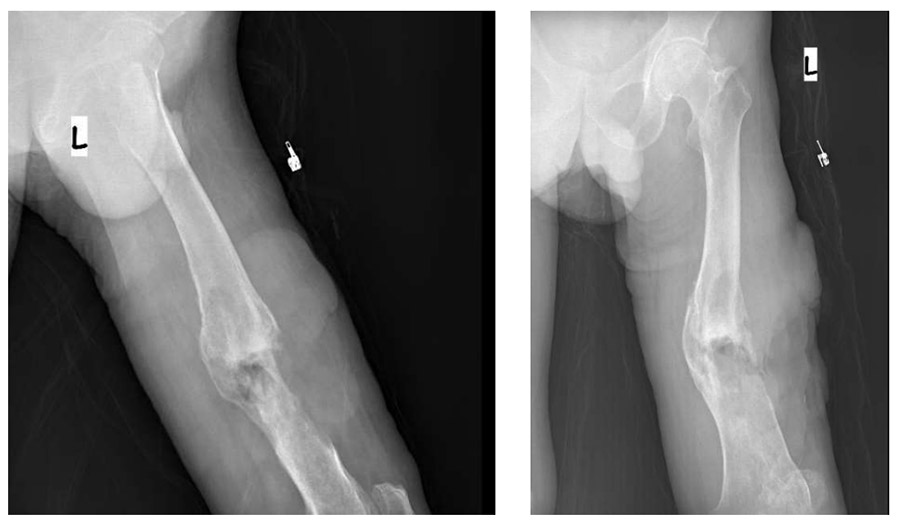

Ameliyat Öncesi: Röntgende kemik harabiyeti ve tümörün yumuşak doku gölgesi görülmekte